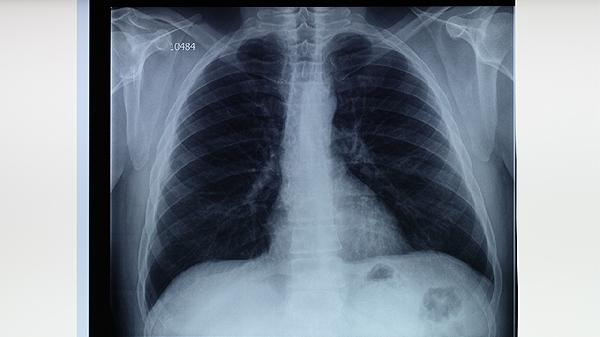

肺結(jié)核的典型癥狀主要有咳嗽咳痰、咯血、胸痛、發(fā)熱盜汗、消瘦乏力等。肺結(jié)核是由結(jié)核分枝桿菌感染引起的慢性傳染病,主要通過呼吸道傳播,當(dāng)出現(xiàn)疑似癥狀時(shí)應(yīng)及時(shí)就醫(yī)進(jìn)行痰涂片檢查、胸部X線或CT檢查等明確診斷。